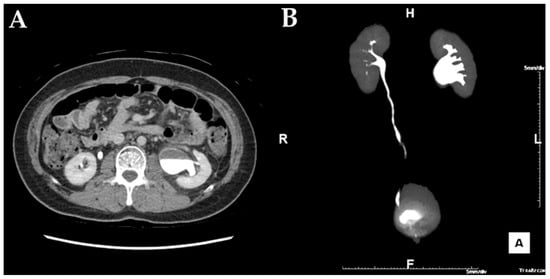

Figure 1. In the abdominal CT, hydronephrosis with a UPJ obstruction on left urinary tract is noted. (A) axial image of the left UPJO, (B) reconstructed coronal image of the left UPJO.

A 34-year-old man with cerebral palsy presented with high fever (39.5 °C), left flank pain for 3 days, and gross hematuria. Twenty years prior, he underwent a ureteroscopic stone removal and ureteral dilation at another hospital and had intermittent episodes of left renal colic and urinary tract infections. Urinalysis revealed the presence of hematuria (red blood cells: 30–50/HPF), pyuria (white blood cells: >50/HPF), and bacteriuria (bacteria: a few colonies/HPF). The C-reactive protein level was 10.3 mg/dL. An abdominal computed tomography (CT) revealed hydronephrosis with a narrowing of the UPJ (Figure 1). A low-density lesion of approximately 1.6 cm with subtle irregular margins in the upper pole of the left kidney, suspected to be a renal abscess, was observed (Figure 2). Urine cytology examinations were performed three times, but all were negative. After 3 days of parenteral antibiotic treatment, the patient became afebrile. The follow-up urinalysis results were normal. A follow-up CT, performed 3 months later, showed that the ill-defined low-density lesion at the upper pole of the left kidney had disappeared. hydronephrosis with a proximal ureteral narrowing was suggestive of ureteral UPJO associated with an improved state of combined ureteritis and a renal abscess. Suspecting recurrent left pyelonephritis due to the UPJO, laparoscopic pyeloplasty was planned. Prior to the pyeloplasty, the patient underwent retrograde pyelography (RGP). The RGP revealed a dilated left renal pelvis and the abrupt narrowing of the UPJ, and there was no filling defect in the left urinary tract. The surgery was performed using a transperitoneal approach. The laparoscopy revealed a UPJO (Figure 3). The dismembered technique was used for the reconstruction of the UPJ. The surgery was completed without complications. A pathological examination revealed that the excised stenotic segment had a UC with an invasion beyond the muscularis propria into the periureteral fat. This pathological stage was pT3, and the grade was high (World Health Organization (WHO) grade 3). Due to the possibility of residual cancer in the remaining ureter, we decided to perform a laparoscopic radical nephroureterectomy with a bladder cuff excision. Two weeks after the laparoscopic pyeloplasty, the patient underwent a second surgery. A pathological examination revealed residual tumor cells in the proximal ureter. The tumor invaded the subepithelial connective tissue (rpT1). The final pathological stage was pT3 with a high grade (WHO grade 3). There was a multifocal urothelial carcinoma in situ in the renal pelvis and mid-ureter. Postoperatively, the patient received four cycles of adjuvant chemotherapy with gemcitabine and cisplatin. The patient has been undergoing regular follow-up sessions without evidence of a recurrence or distant metastasis for 2 years.